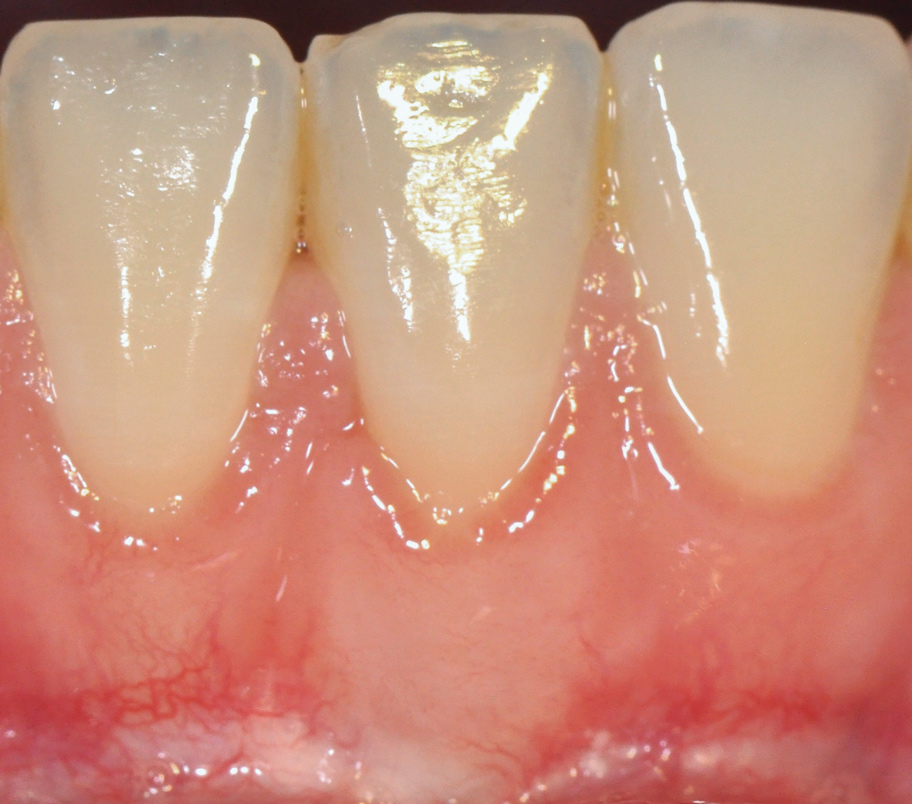

The workshop's group on periodontal soft-tissue root coverage procedures evaluated the predictability of root coverage procedures for single- and multiple-tooth Miller Class I and II10 periodontal recession defects. The workshop concluded that predictable root coverage was possible for Miller Class I and II recession involving a single tooth. When compared with the use of acellular dermal matrix graft (ADMG) (donor tissue) or EMD (porcine origin), procedures using a subepithelial connective tissue graft (SCTG) harvested from the patient's palate provided the best root coverage outcomes in conjunction with a coronally advanced flap.11 As alternatives to autogenous donor tissue, the workshop found strong evidence to support the use of an ADMG or EMD in conjunction with a coronally advanced flap and limited evidence to support the use of platelet-derived growth factor and xenogeneic collagen matrix.11 In addition, root coverage procedures were found to be effective for Miller Class I and II recession defects affecting multiple teeth, although the evidence is limited.11 Figure 1 and Figure 2 show the pretreatment and 1-year postoperative views of a soft-tissue root coverage treatment with SCTG and EMD that used a coronally advanced flap and a tunneling procedure. Figure 3 and Figure 4 depict the pretreatment and 3-year postoperative views of a root coverage procedure with ADMG and EMD that used a coronally advanced flap and a tunneling procedure (this patient was noncompliant following surgery and did not return to the office until the 3-year postoperative appointment).

(1.) Pretreatment view of single incisor with gingival recession exposing the root.

Figure 1

(2.) Postoperative view after one year following treatment with SCTG (harvested from palate) and EMD using a coronally advanced flap and a tunneling procedure.

Figure 2